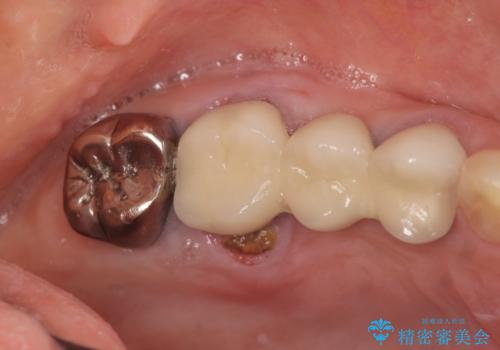

- 「噛むと歯に痛みを感じる、噛めない。」、と痛みの改善を希望され来院されました。

X線写真検査を行ったところ、ブリッジ支台の歯が破折(割れている状態)し抜歯が必要な状態です。

抜歯をしたのちしっかりと咬合力を回復し前後の歯を守るためにも、入れ歯やブリッジではなくインプラントによる咬合機能回復を計画します。